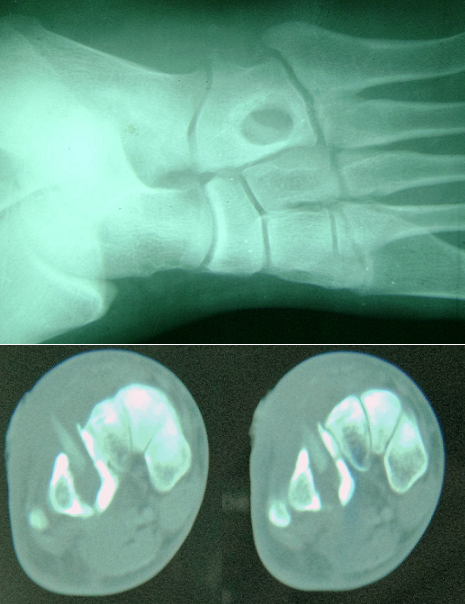

This is a patient aged 35 years old, farmer, who consults for chronic fistula of the soles lasting for three months without any notion of trauma. The review found a swelling of the outer edge of the foot of inflammatory appearance with pus coming through a fistula at the top. Plain radiography shows a well limited round osteolysis recalling the appearance of an abscess of Broca. The scanner confirms the osteolysis and highlights intra-osseous foreign body. The patient underwent surgical treatment by trimming, removal of a piece of wood and curettage of the bone cavity. The outcome was favorable with disappearance of infectious signs and filling the bone cavity.